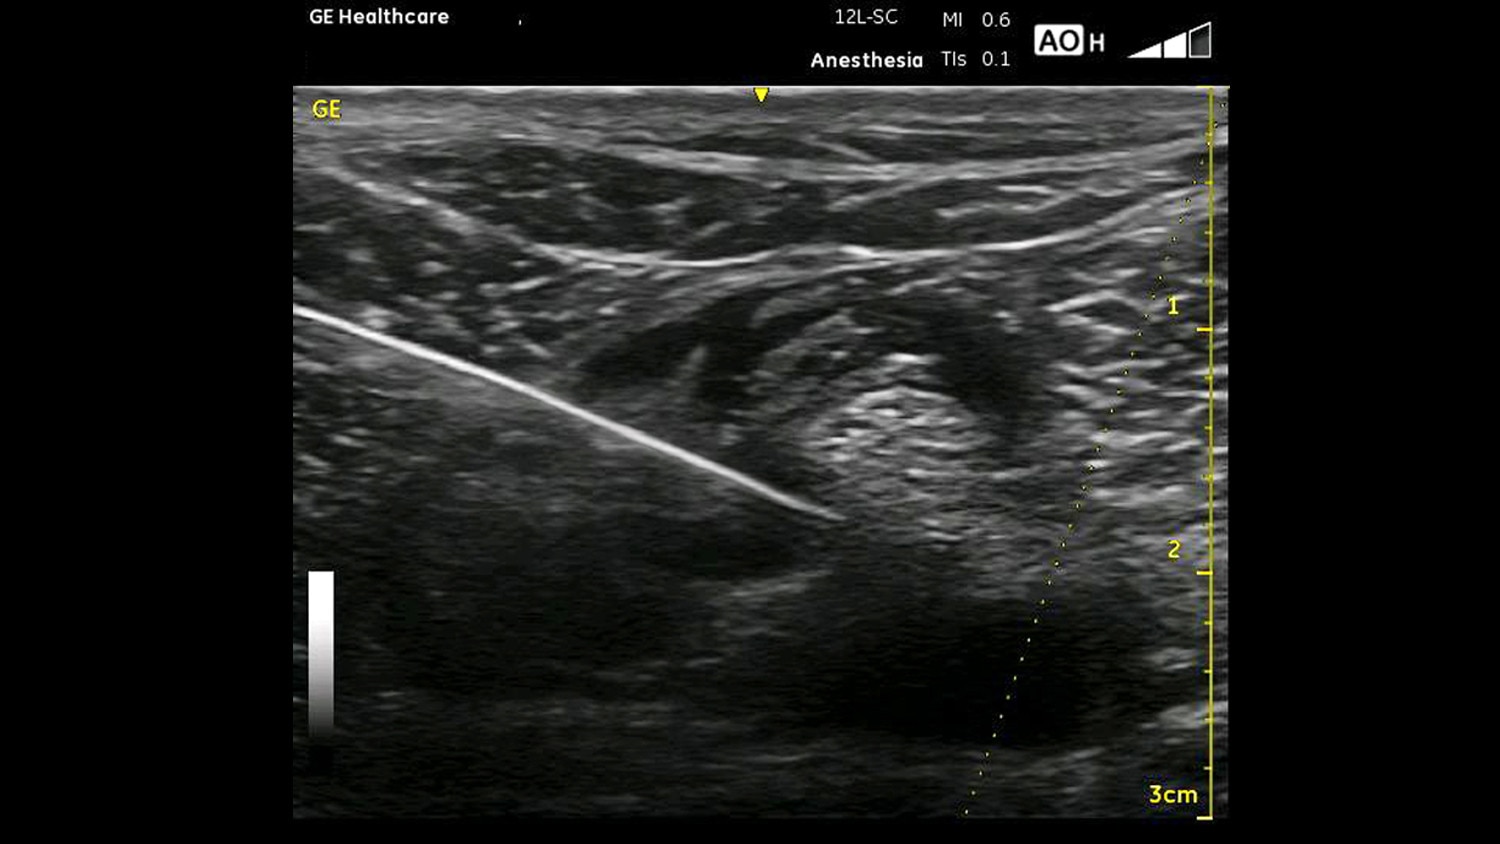

Regional Anesthesia